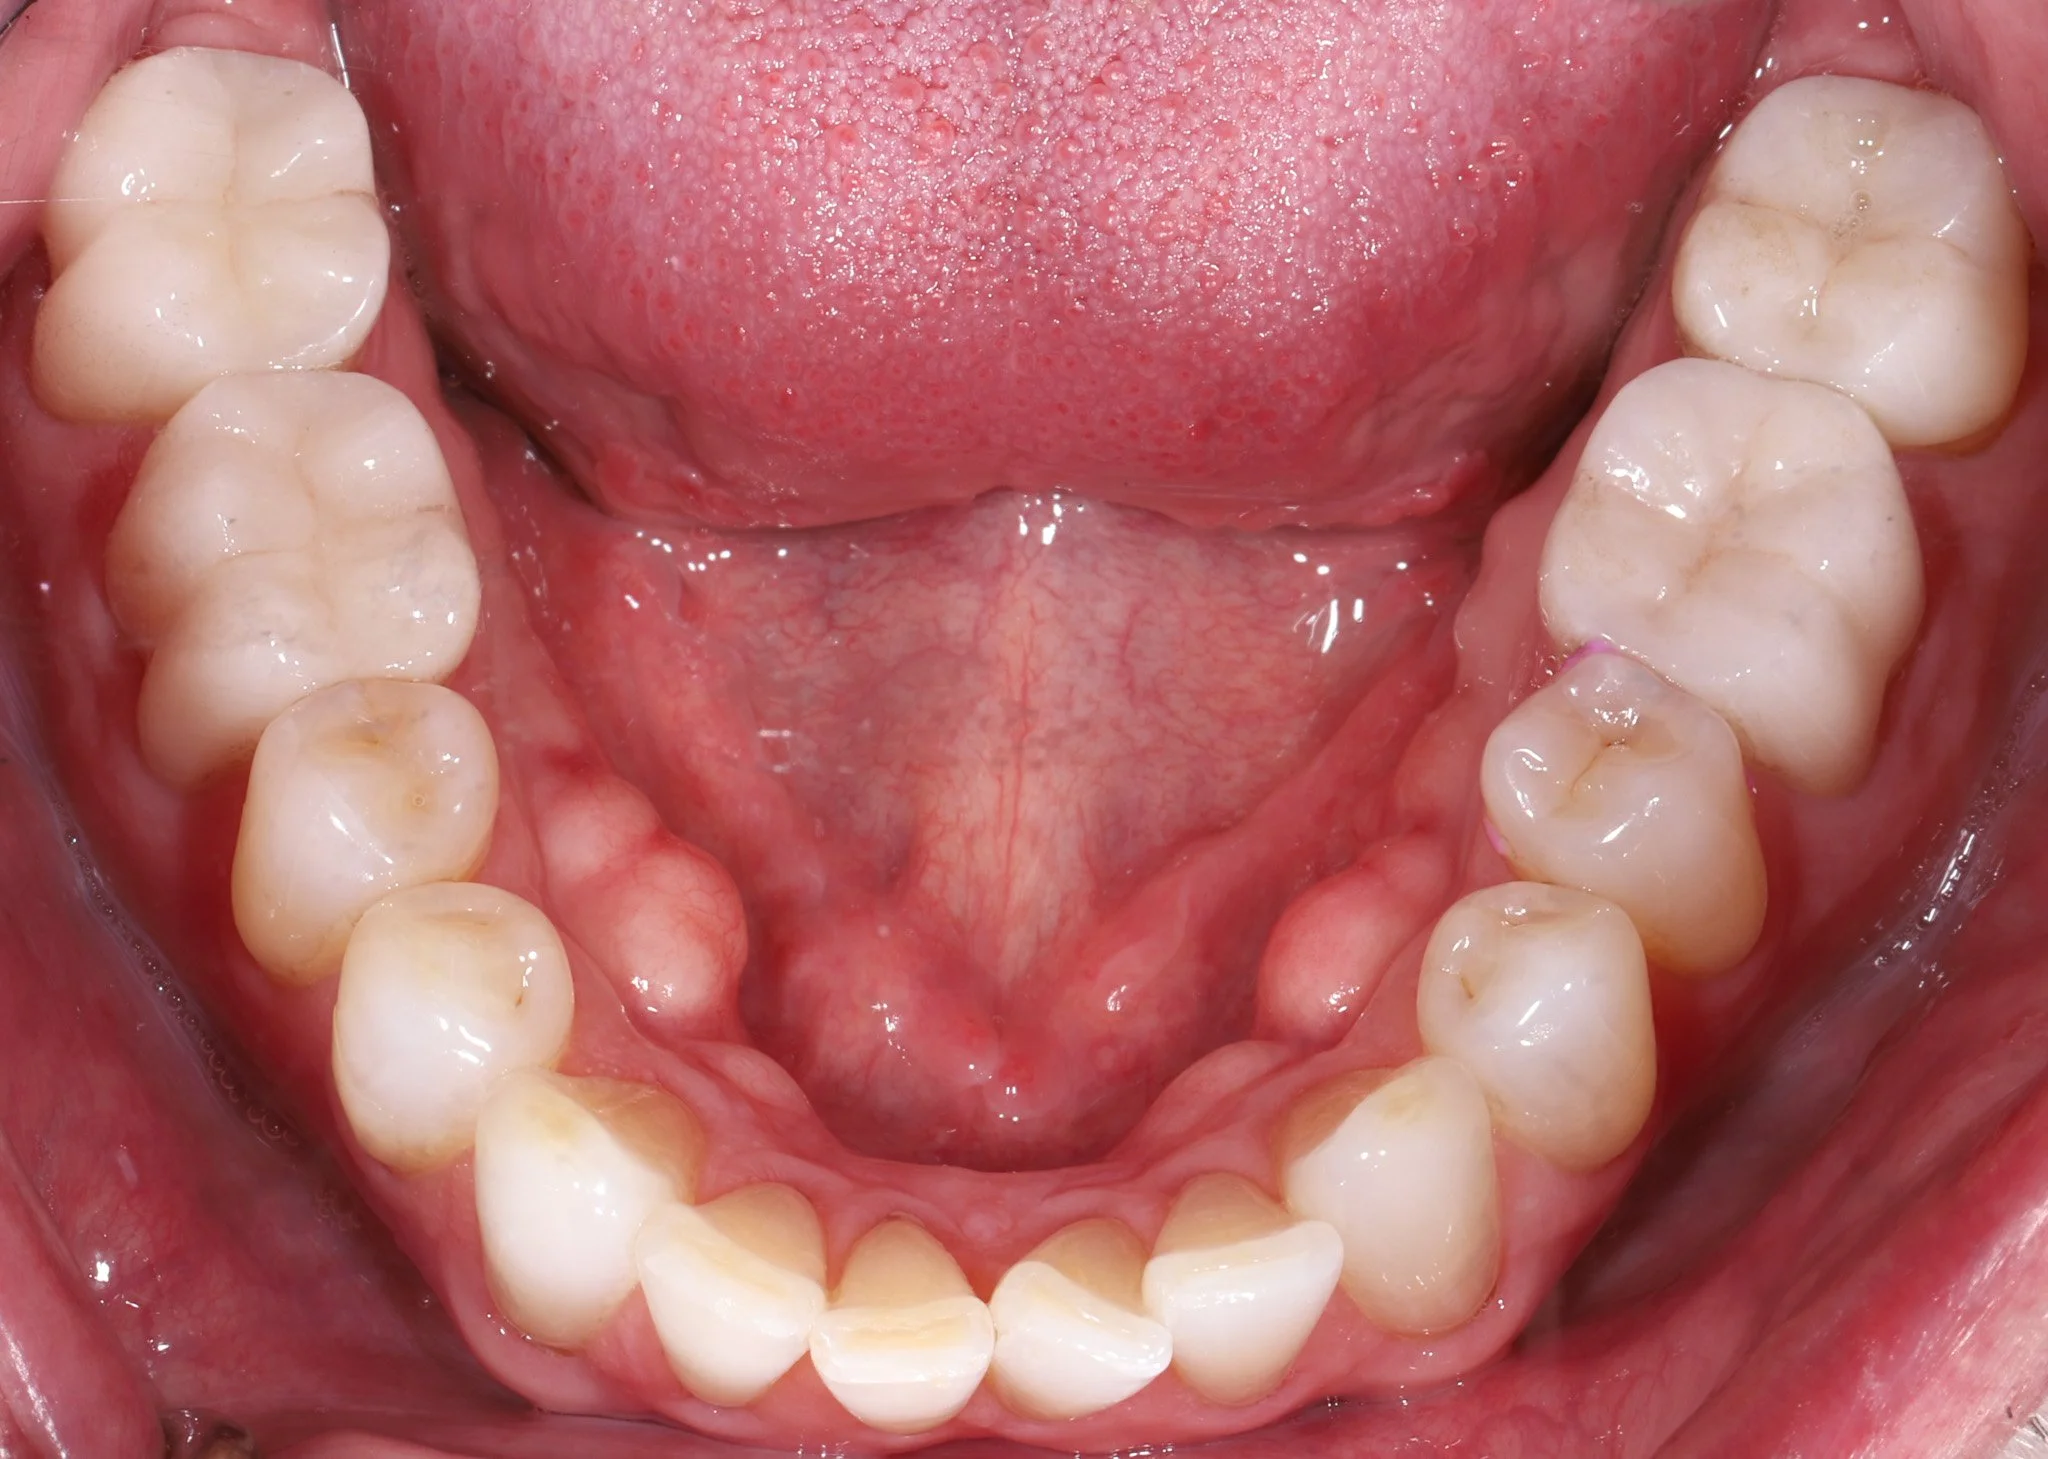

Close-up of the lower teeth showing decay and acid erosion.  Prior to restorative treatment.

Before: Back 2 teeth each side have decay, acid erosion, wear

Close-up of the restored teeth with bonded porcelain crowns that fit and blend with natural dentition.

After: Bonded porcelain restorations to seal and protect teeth while adding back missing structure